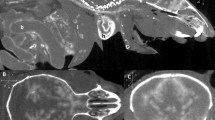

Transmission electron micrographs from the transverse sections of the PMA-stained intervertebral discs. (A) The annulus-nucleus interface confirms the abundance of collagen fibers in the annulus fibrosus with a transition in PMA-intensity and nano-scale structure towards the nucleus pulposus. (B) Within the nucleus pulposus, there’s a lack of PMA staining that is consistent with very low presence of collagen in this region. (C) The annulus fibrosus is collagen rich and can be confirmed by both the PMA-staining and the characteristic banding of collagens. (D) The notochordal remnants region appear to contain small amounts of collagen.